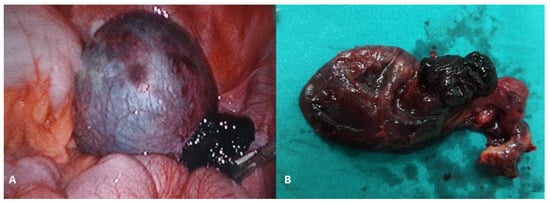

Figure 5.

A 17-year-old female patient presented to a pediatric endocrinologist for primary amenorrhea. After diagnostic evaluation, the endocrinologist diagnosed a female phenotype and a male karyotype (46, XY). The MR scan of the abdomen showed a tumor in both gonads. The left gonad looked like a testis and the right one like an ovary. A diagnosis of a disorder of sexual development (DSD) was made. A bilateral laparoscopic adnexectomy was performed. The pathohistological examination revealed a bilateral gonadoblastoma with components of a dysgerminoma. No gonadal tissue was present in either of the removed specimens. TNM: T1bNXMX; Figo classification: 1b; (A) Intraoperative findings; (B) Macroscopic specimen after bilateral adnexectomy. Source: Archive of the Department of Pediatric Surgery, University Hospital of Split.